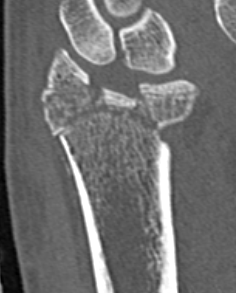

Distal radius fracture with shortening and dorsal tilt

Articular incongruency > 2 mm

Sigmoid notch disruption and DRUJ instability